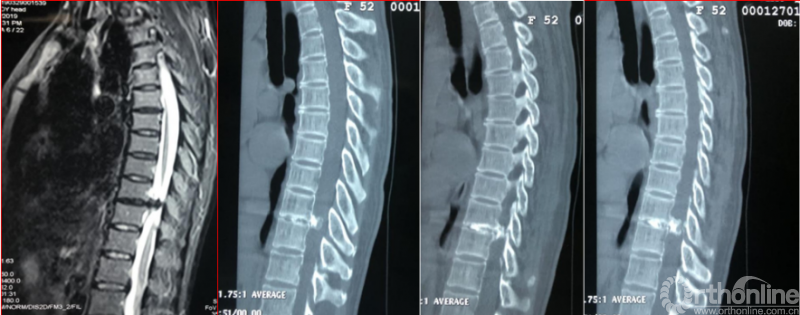

术后第二天资料

术后影像学资料

术后资料